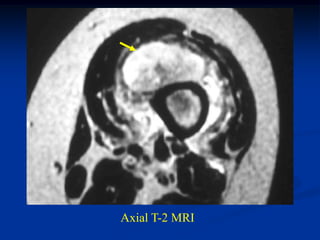

Case #265                  Axial T-2 MRI

blood

65 year old female with large hematoma in MFH thigh

tumor

Axial proton density MRI

muscle

Axial T-2 MRI

Coronal T-1 MRI